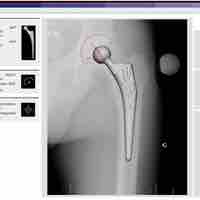

Arthroplasty is an operative procedure in which the arthritic or dysfunctional joint surface is replaced or repaired.